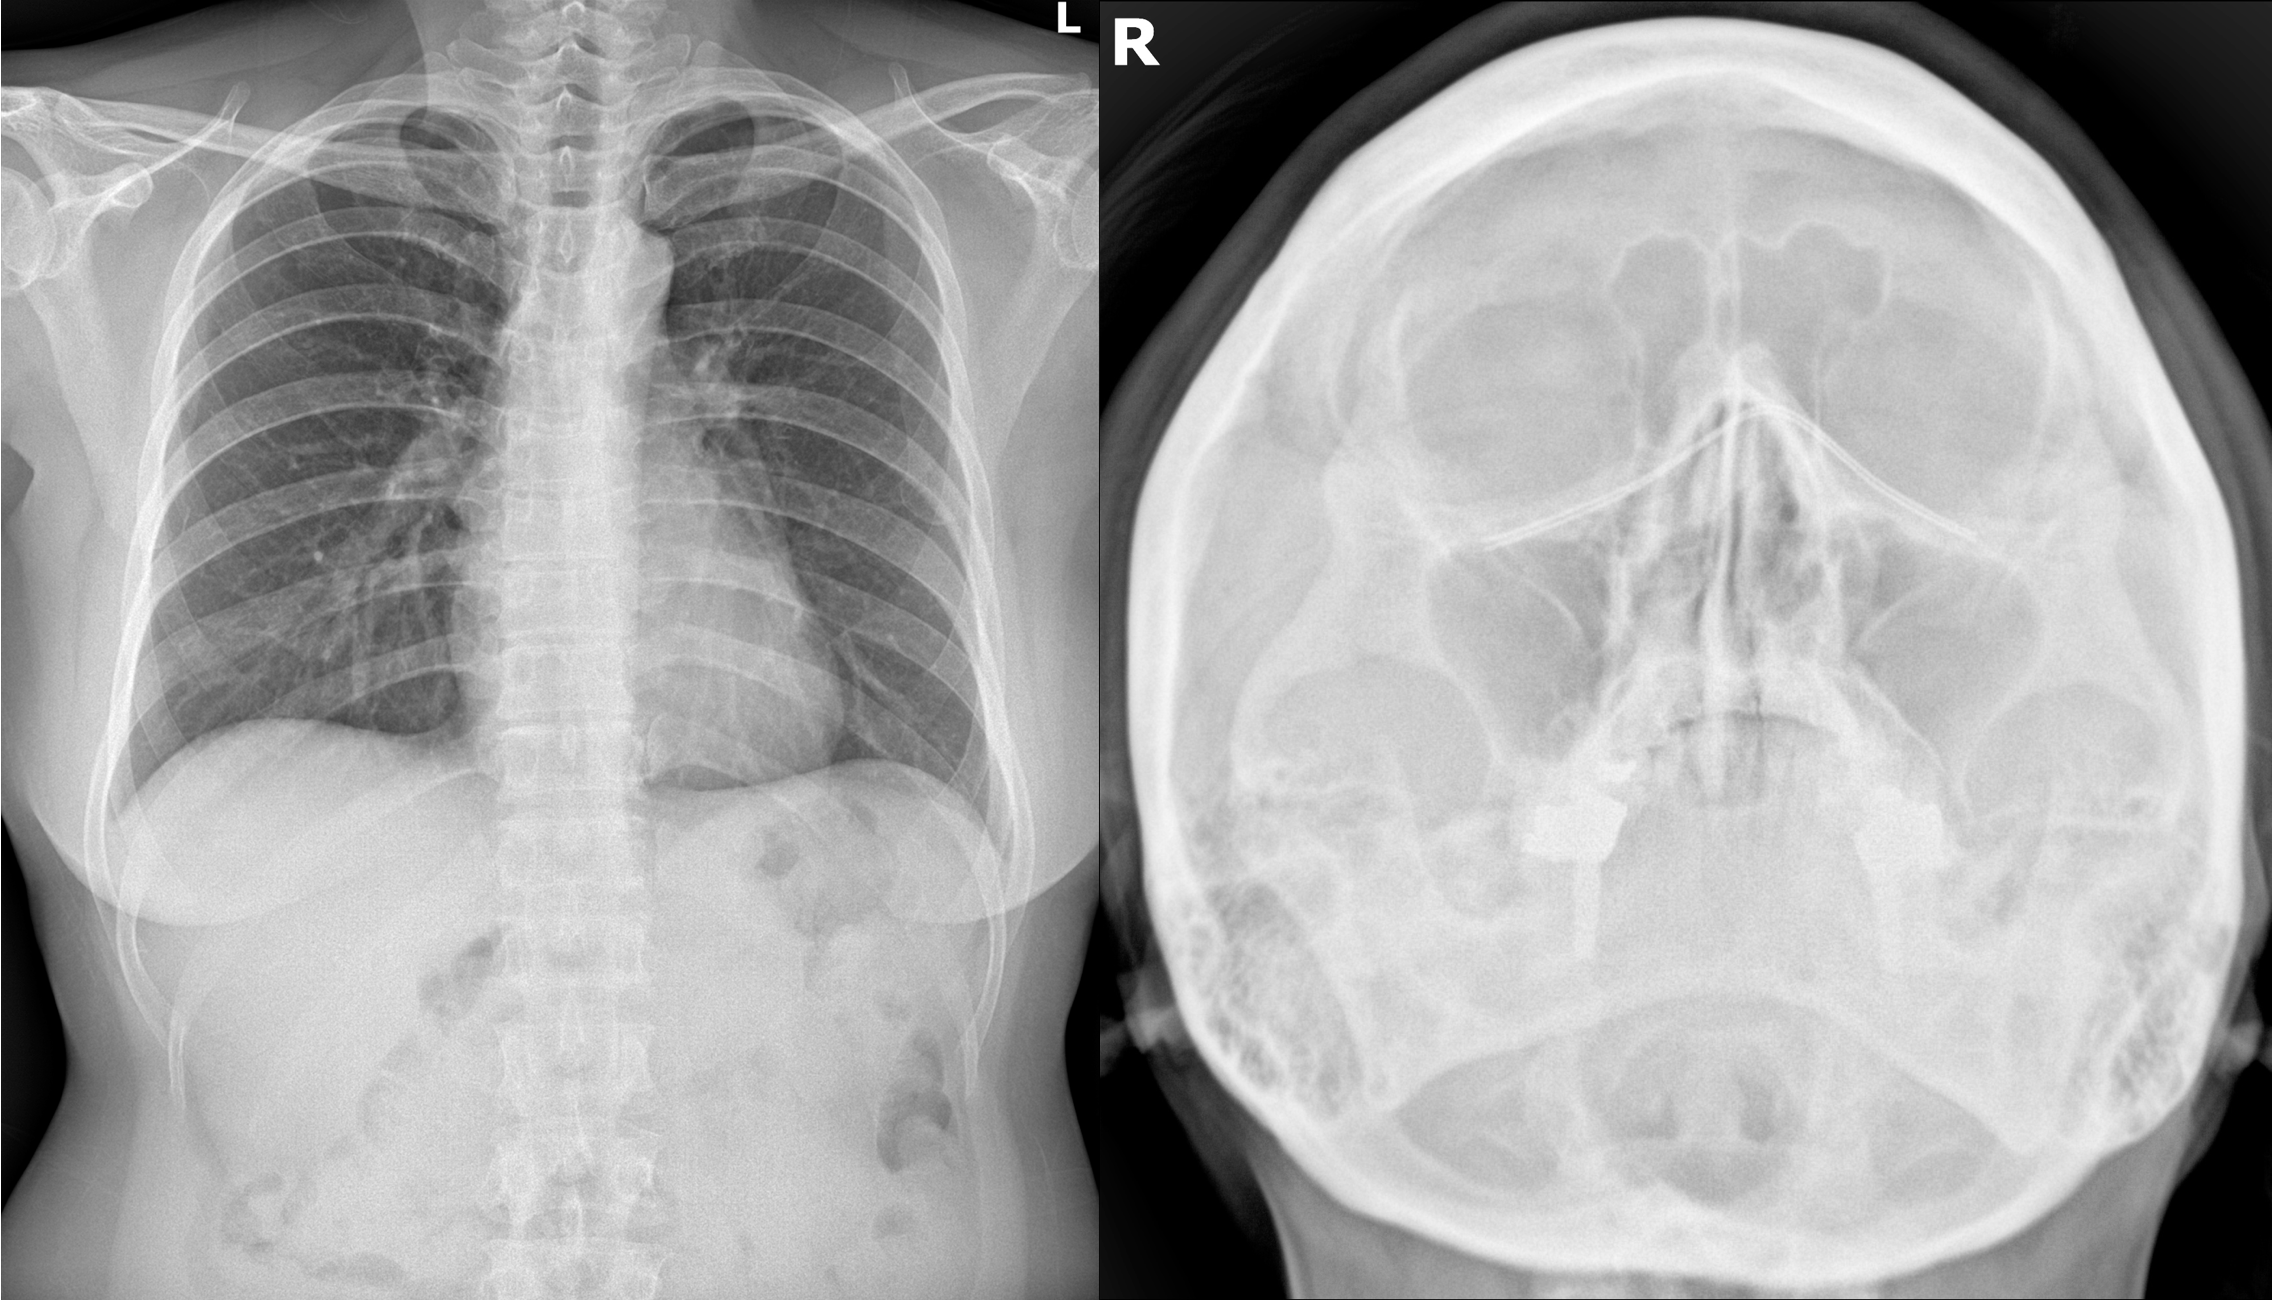

만성 기침 환자의 흉부 CT 검사

만성 기침 환자의 폐기능 검사; (A) 폐활량측정(Spirometry); (B) 기관지 수축 유발검사(Bronchial provocation test);